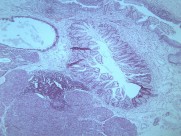

一般认为畸胎瘤多系个体发育初期,部分多能性原始细胞迷离出来,在纵隔内增殖发展成肿瘤。这类肿瘤以良性畸胎瘤多见。常位于前纵隔。畸胎瘤多为实质性,可同时存在大小不等的囊腔,内含外、中或内胚层组织的衍生物如毛发、牙齿、软骨、平滑肌、支气管或肠壁等。部分畸胎瘤可以恶变。由未分化成熟组织构成的畸胎瘤属恶性,呈浸润性生长。畸胎瘤与邻近组织粘连或穿破入邻近脏器如肺、支气管,病人可咳出毛发或皮脂样物。皮样囊肿是一种单房或多房薄壁囊肿,因囊内多衬以鳞状上皮及其附属物而得名。囊内有结节状物、毛发及皮脂类物。